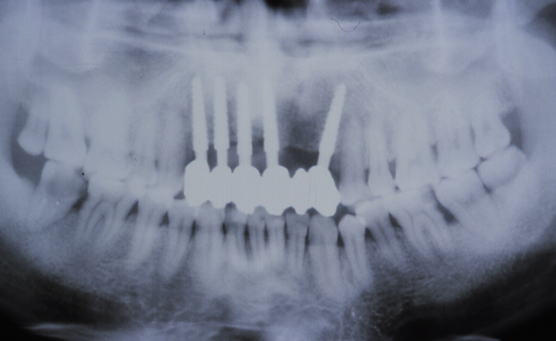

症例101